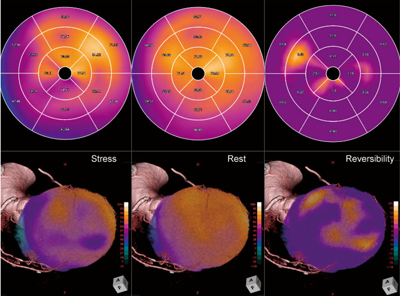

糖尿病などによる高度石灰化症例では、冠動脈CTでの評価が困難となるが、びまん性の狭窄病変を複数有していることも多く、虚血に関する責任冠動脈の同定が困難となる場合がある。これは、狭窄や閉塞病変の出現によって、複雑な心筋血液灌流状態となってしまっている冠動脈バイパスグラフト術後でも同様である。この様な症例に対して、ziostation2の“CT/SPECT心臓フュージョン”を用いて、責任冠動脈の同定を行っている。

図6は、左前下行枝にバイパスされた右内胸動脈の閉塞と、右冠動脈の後下行枝にバイパスされた大伏在静脈に狭窄が認められた症例であり、ほかにも数か所に狭窄病変が認められたが、心筋血流SPECTでは、心室中隔および心尖部を中心にパッチーな再分布を認める虚血領域が描出された。心室中隔の領域は、左前下行枝閉塞部手前の狭窄病変によるものと推測され、心尖部は主に右内胸動脈の閉塞によるものと考えられるが、一部の下壁側に関しては、心尖部側まで分布する右冠動脈の後下行枝も責任冠動脈である可能性がフュージョン画像から確認された。

図6 “CT/SPECT心臓フュージョン”を用いた責任冠動脈の同定

心尖部に認められる虚血領域は、左前下行枝にバイパスされた右内胸動脈の閉塞によるものと考えられるが、下壁心尖部の虚血領域は、大伏在静脈でバイパスされた右冠動脈の後下行枝である可能性も考えられた